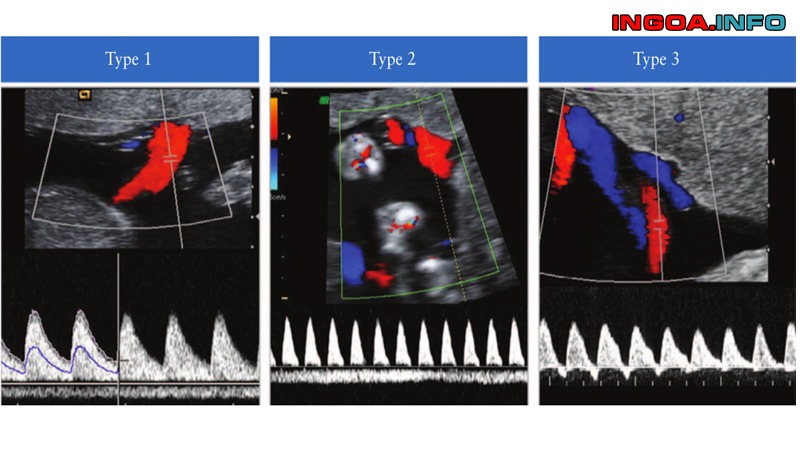

3.3. Doppler động mạch tử cung:

Để tầm soát thực trạng suy yếu nhau thai vào tuần lễ 18-22. Hãy triển khai siêu âm Doppler động mạch tử cung. Thông thường vẫn còn thấy chỗ khuyết (notch) ở quá trình tâm trương. Sau tuần thứ 22, chỗ khuyết này mất đi tương ứng với đợt xâm lấn thứ 2 của tế bào nuôi vào thành động mạch. Nếu chỗ khuyết này còn sống sót chứng tỏ sự xâm lấn không không thiếu. Rủi ro tiềm ẩn thai bị IUGR hoặc mẹ bị cao huyết áp thai kỳ.

Sau 26 tuần, phổ Doppler động mạch tử cung không còn khuyết tâm trương, S / D ratio 2,5. Sau 28 tuần, gọi là suy tuần hoàn nhau thai khi sống sót chỗ khuyết. Hay nặng hơn là sóng đảo ngược tiền tâm trương, S / D ratio > 2,5.

Trong tiến trình cuối ba tháng giữa hoặc đầu ba tháng cuối của thai kỳ. Nếu hoài nghi thai bị IUGR, siêu âm Doppler màu động mạch tử cung, động mạch rốn và động mạch não giữa hoàn toàn có thể giúp cho chẩn đoán, và nhìn nhận thực trạng suy yếu nhau thai .